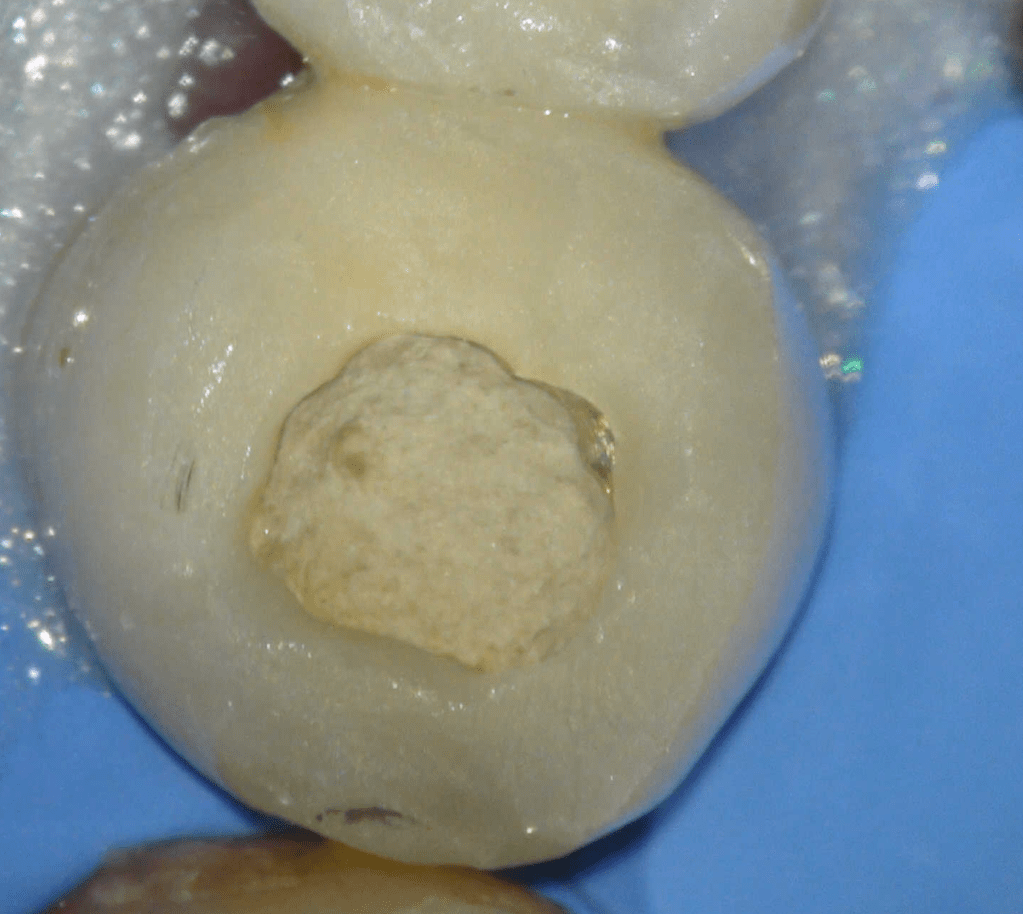

Fisura, remoción amalgama para explorar